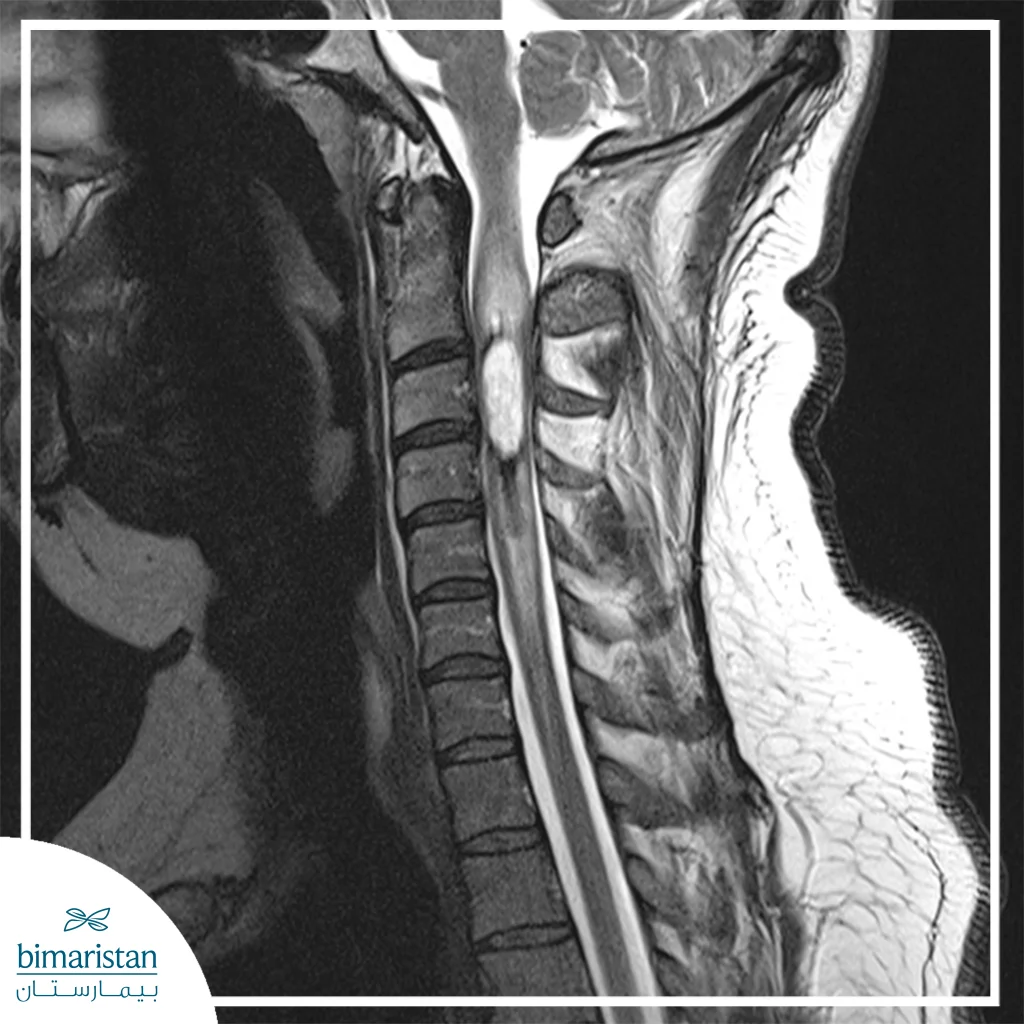

- تقييم الحالة الطبية للمريض: يتم تقييم شامل لحالة المريض باستخدام الفحوصات مثل الأشعة السينية أو الرنين المغناطيسي، هذا التقييم يساعد في تحديد موقع الورم ومدى تأثيره على العظام أو الأعصاب المحيطة.

- مراقبة النتائج والشفاء: بعد حقن الخلايا الجذعية، يتم متابعة المريض بشكل دوري باستخدام الأشعة السينية أو الرنين المغناطيسي لضمان أن الخلايا الجذعية تقوم بدورها في تحفيز النمو.